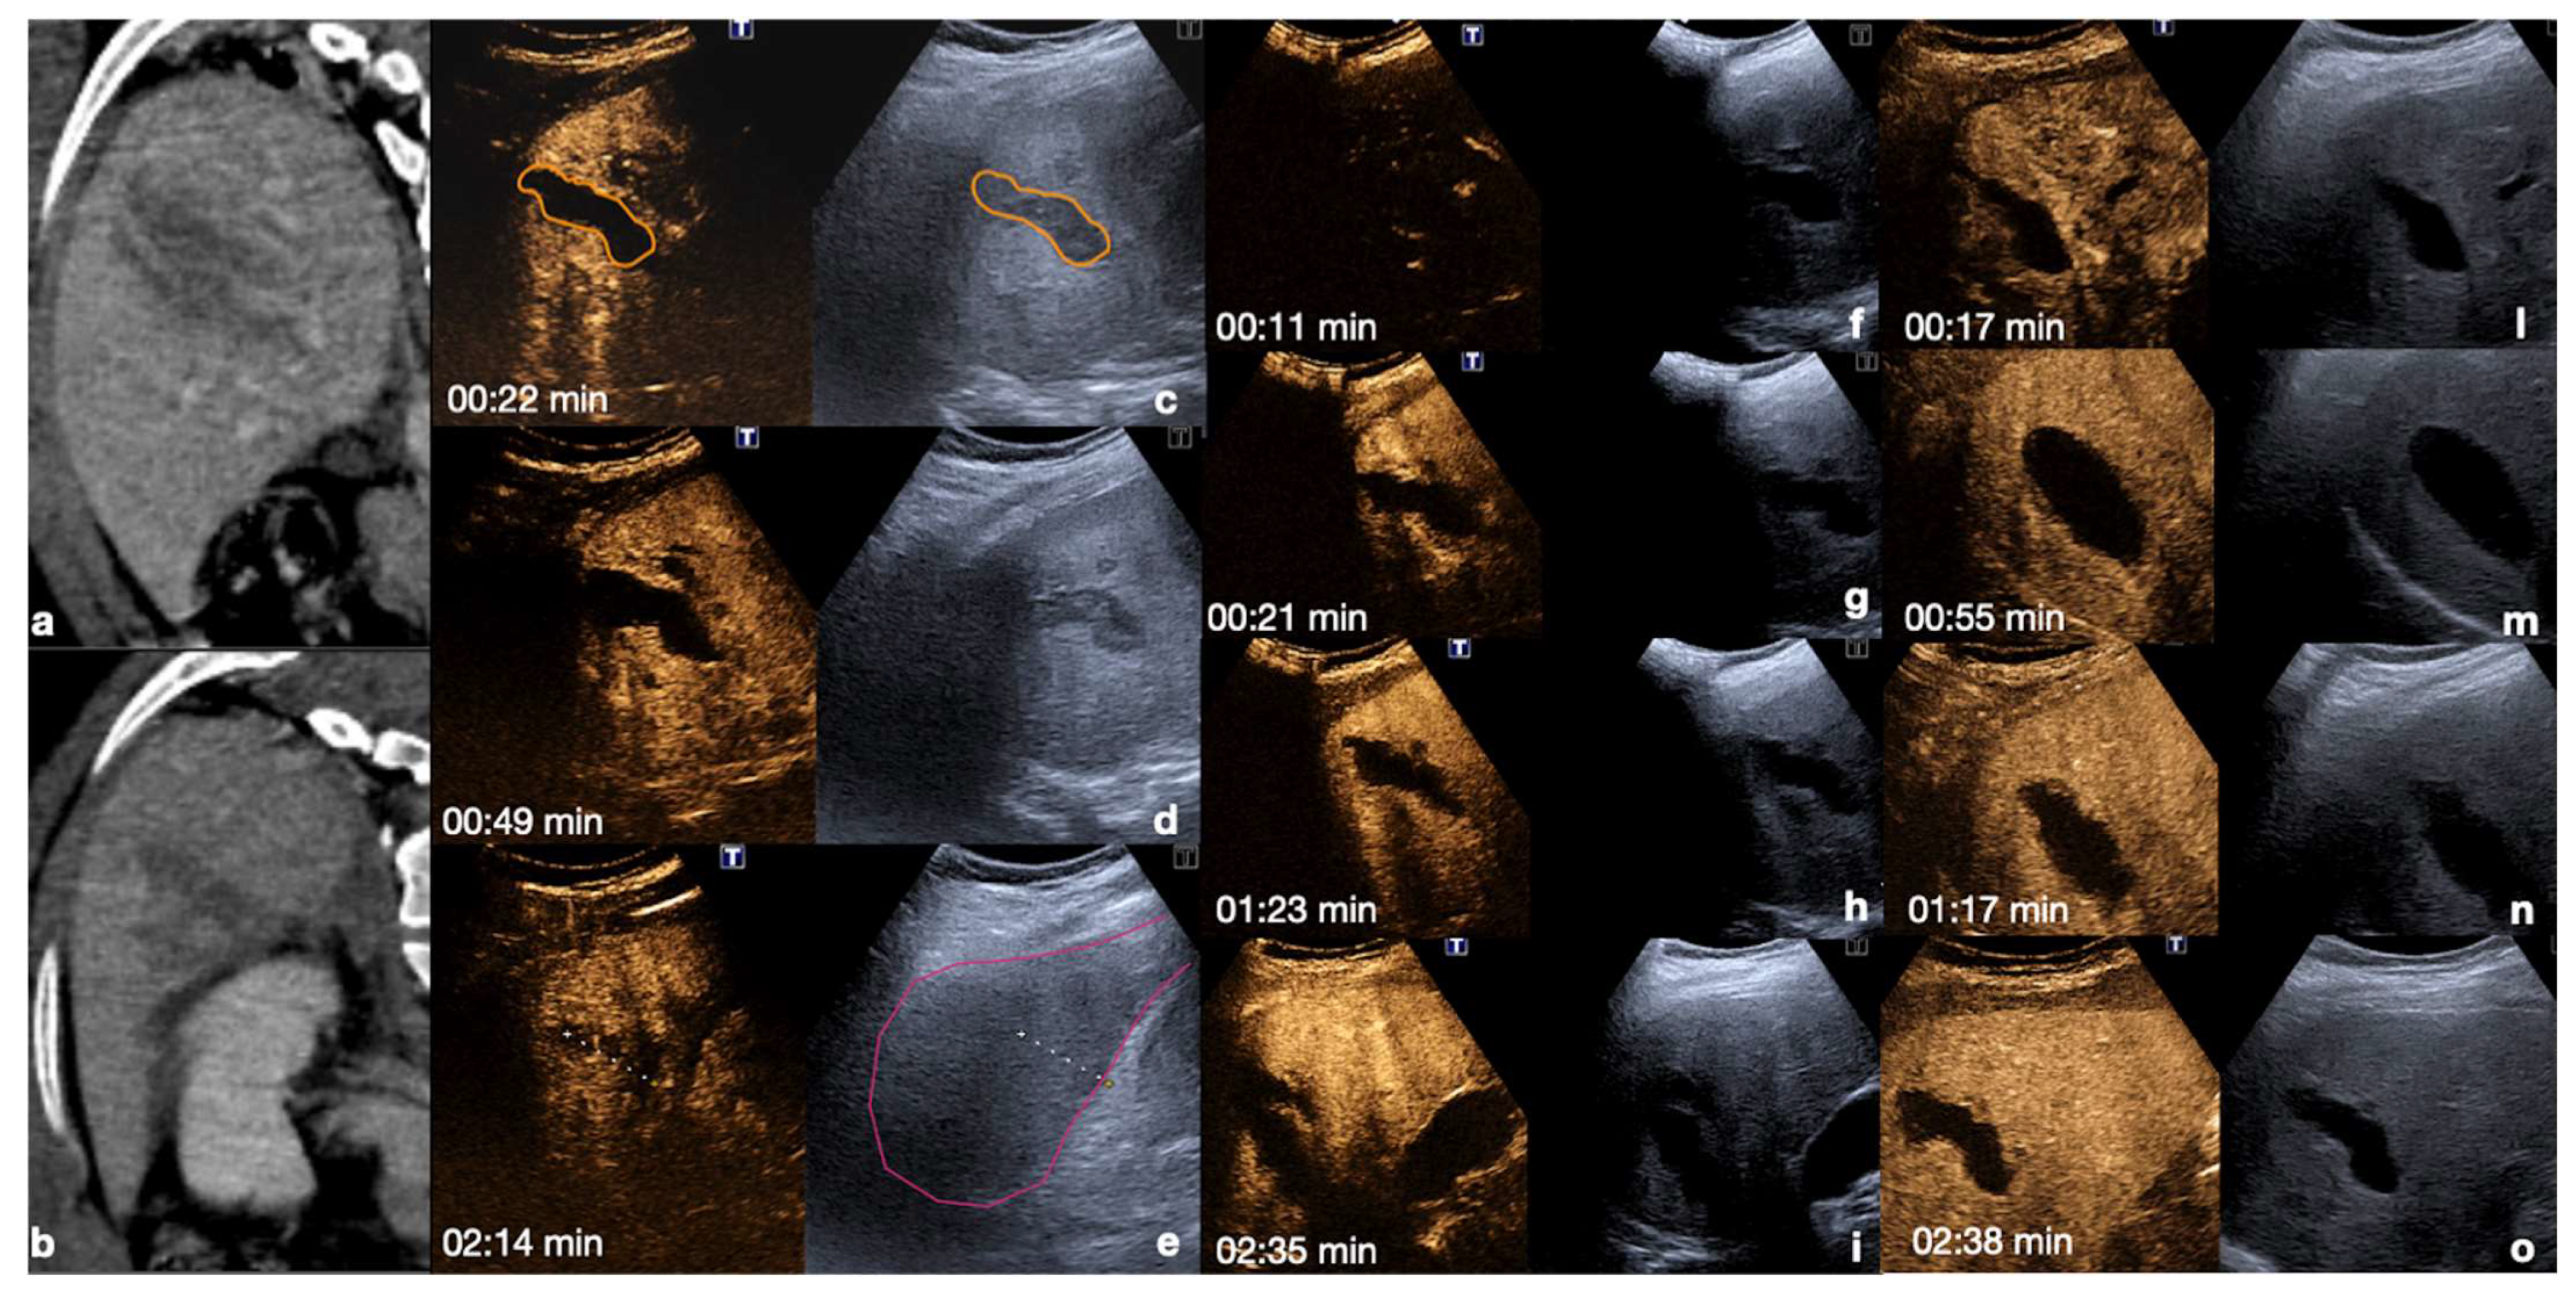

- Parenchymal injuries:

2.3.2. Vascular Injuries

- Active bleeding:

- Contained vascular injuries:

| 10–20 s (early) 20–40 s (late) | Arterial phase: best depiction of contained vascular injuries, such as pseudoaneurysms and arteriovenous fistulas in the early phase. |

| 2–6 min | Venous-late phases: distribution of the contrast in the whole organ. Best time to depict parenchymal injuries. |

| Flash mode | Destruction of bubbles and possibility to re-evaluate an area of interest. |